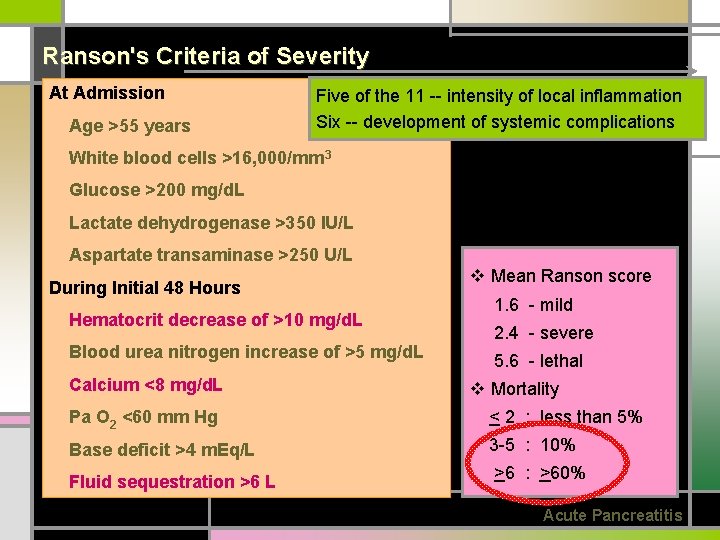

Ranson's Criteria of Severity At Admission Age >55 years Five of the 11 -- intensity of local inflammation Six -- development of systemic complications White blood cells >16, 000/mm 3 Glucose >200 mg/d. L Lactate dehydrogenase >350 IU/L Aspartate transaminase >250 U/L During Initial 48 Hours Hematocrit decrease of >10 mg/d. L Blood urea nitrogen increase of >5 mg/d. L Calcium <8 mg/d. L v Mean Ranson score 1. 6 - mild 2. 4 - severe 5. 6 - lethal v Mortality Pa O 2 <60 mm Hg < 2 : less than 5% Base deficit >4 m. Eq/L 3 -5 : 10% Fluid sequestration >6 L >6 : >60% Acute Pancreatitis